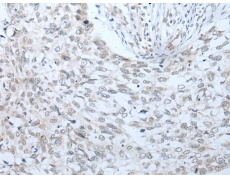

IHC positive control: |

Human lung cancer |

IHC Recommend dilution: |

20-100 |